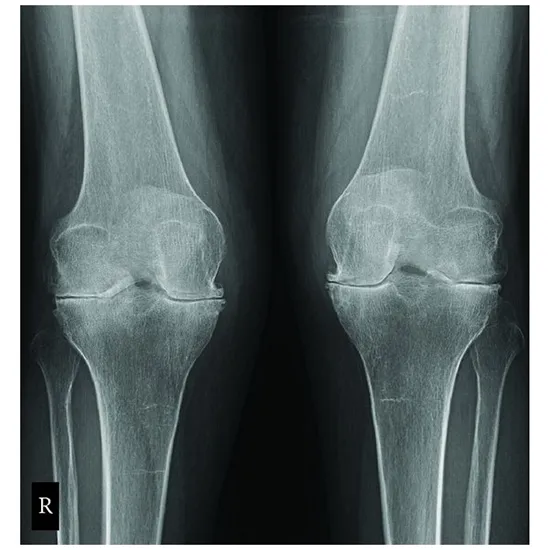

X Ray Both Knee Tunnel View

X-Ray both knee tunnel view is a radiography procedure that is used to obtain the frontal view of the knee with the knee flexion of 60 degrees. It can be obtained posteroanterior (PA) with the patient prone or kneeling on the recorder, or AP with the patient on their back. In this procedure, the position of the tibia is directly in the path of the x-ray beam.